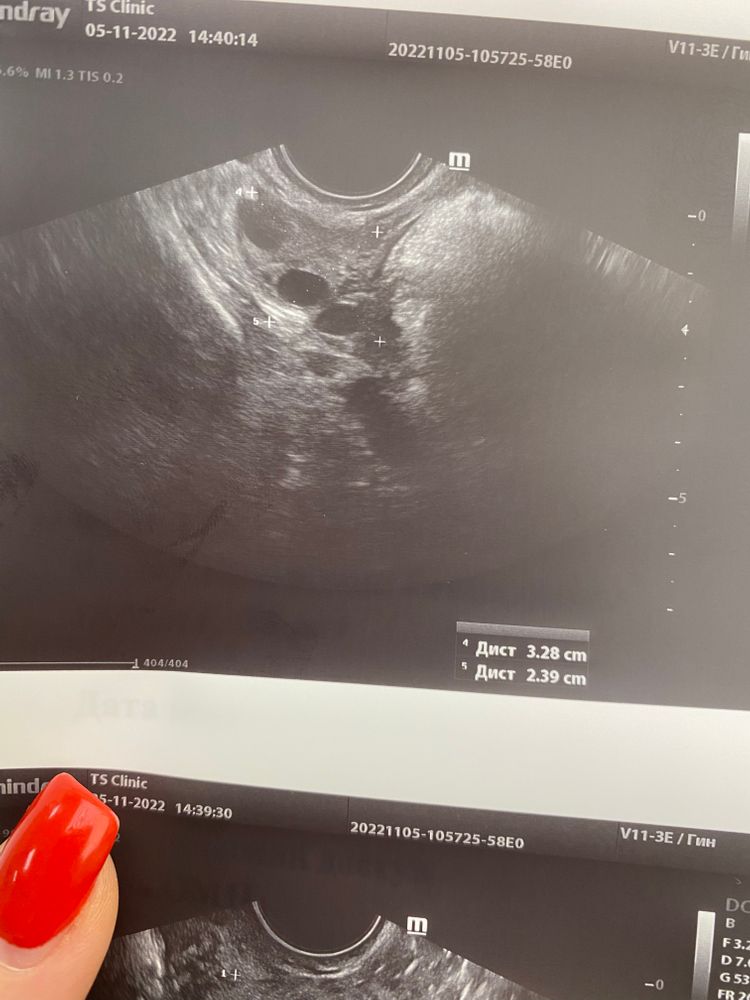

3дц и амбициозные планы на ноябрь!)) у меня на всех последних УЗИ левый трудится, правый тоже молодец, но не успевает за левым 🙈

У нас планы на ноябрь 😻у меня 4й день дпо, или14й дц . Трудяга левый яичник 😆да такой трудяга, что О с кровоизлиянием часто) болит по несколько дней во время О.